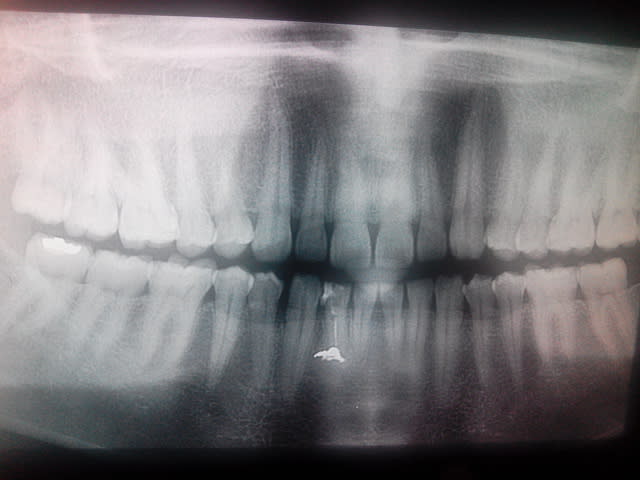

Avec plein de panoramiques sortie de nulle part, des questions élémentaires posées avec aplomb, des expression d'un autre temps telles que :

"dent arthritique" <=> incapacité à faire le diagnostic. "dent barrée" <=> incapacité à faire l'avulsion.

Faut déjà arrêter le lentulo surtout quand on a pas de notion de ce qu'est une longueur de travail! -)))

T'aimes pas ce joli puff apicale ou devrais-je dire cette jolie bouse apicale? :-)

Tu souleves,tu grattes, tu refermes.

Mais d'abord tu refais l'endo. Et tu nous envoie la prochaine question.